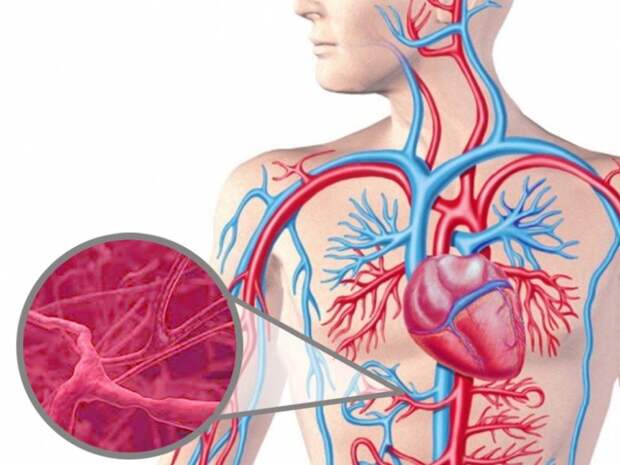

Васкулит – серьезное заболевание сосудов, причины которого до сих пор остаются загадкой для современной медицины. При обострении воспаляются стенки вен и капилляров, нарушается кровоснабжение внутренних органов.

Заболевание относится к аутоиммунным и мало изучено врачами. Оно связано с воспалением кровеносных сосудов, может затрагивать крупные вены и мельчайшие капилляры. Среди возможных причин обострения